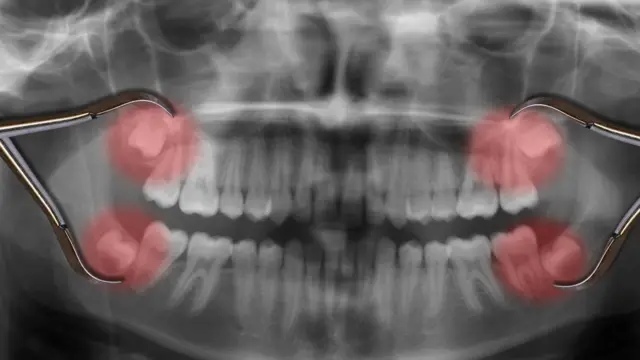

4. Las muelas del juicio

Pero hay un tipo de diente del que podríamos prescindir: las muelas del juicio. Están en la parte posterior de la mandíbula y se desarrollan a medida que envejecemos. Generalmente aparecen cuando llegamos a la edad adulta.

Nuestros antepasados las usaban para masticar plantas pero hoy ya no los necesitamos para nada.

El problema que generan es de espacio. No tenemos espacio suficiente para ellos en nuestras mandíbulas, lo que significa que generalmente empujan a los demás dientes mientras se abren camino a la superficie y esto puede llegar a ser muy doloroso.

La culpa de no tener suficiente espacio es del cerebro, que se ha hecho más grande con el tiempo, modificando la forma de nuestra cabeza.